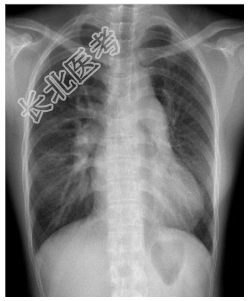

- [材料题] 患者,女性,25岁,发现心脏杂音24年,伴活动后气促1年余。查体.左侧第二肋间喷射性杂音,第二心音亢进,固定分裂。行胸部平片检查。

- 简答题1、诊断及依据是什么?

- 简答题2、鉴别诊断有哪些?